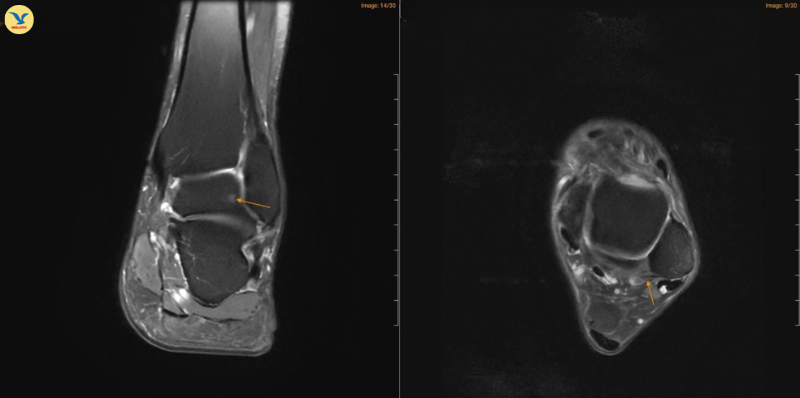

MRI chân trái ghi nhận hình ảnh thoái hóa khớp và phù nề

Đồng thời ghi nhận hình ảnh tổn thương gai xương thoái hóa khớp cổ chân trái, ổ phù tủy xương vị trí xương sên, phù nề dây chằng chày mác sau, dây chằng sên mác sau, dây chằng gót chày và dây chằng tam giác cổ chân, dịch khớp cổ chân, phù nề phần mềm quanh khớp cổ chân.